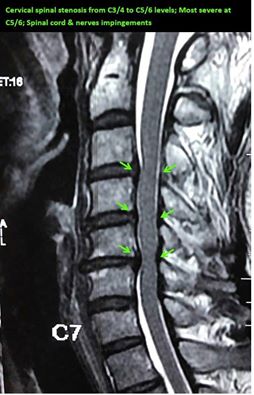

脊髓和神經根受压症状

颈部疼痛和神经根受压导致手臂疼痛

轻度脊髓受压征兆